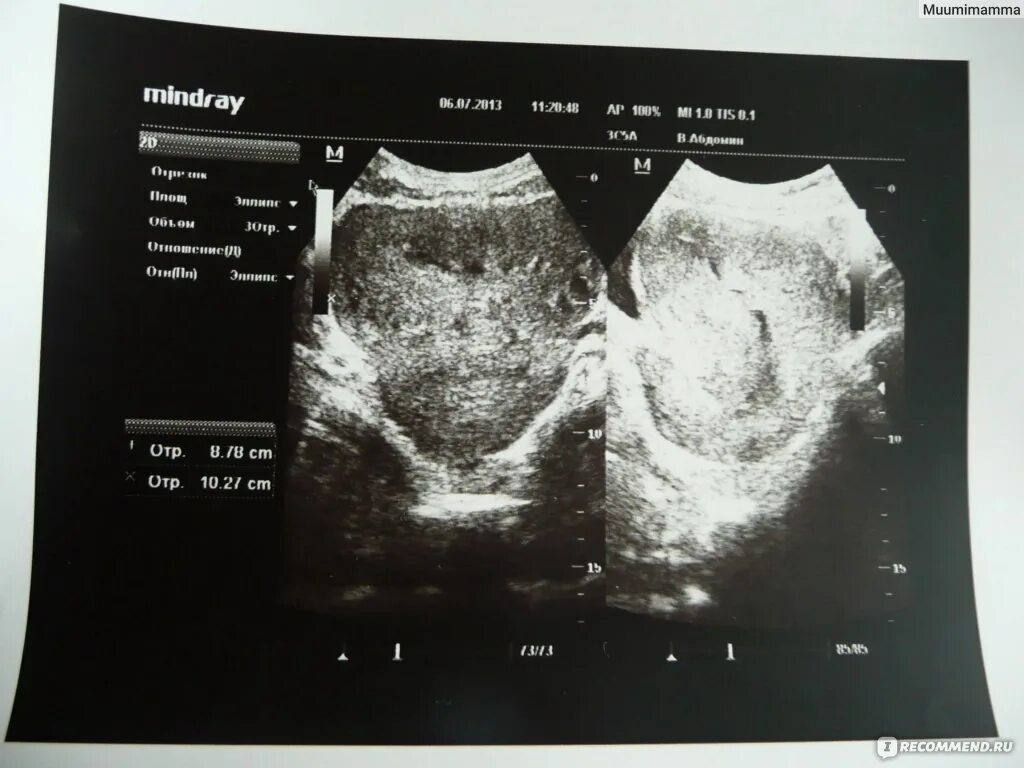

Узи при месячных